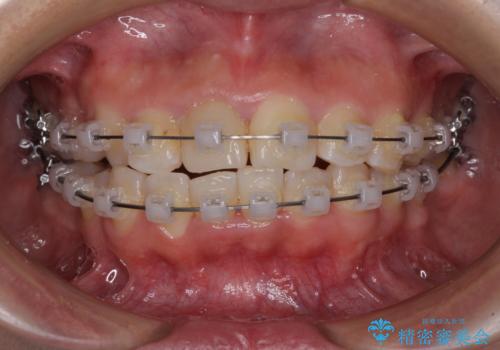

虫歯と抜いたままの奥歯とデコボコの前歯 総合歯科治療

- 放置した虫歯や抜いたままの奥歯、前歯のデコボコを気にして来院された患者様です。

口元の突出感は少なく、下顎の叢生は軽微なものであったので、叢生の強い上顎左右の小臼歯を1本ずつ抜歯し、ワイヤー装置にて矯正治療を行うこととしました。

矯正治療を行う前に、根管治療の必要な上顎前歯と下顎大臼歯の根管治療を行い、矯正治療の途中で下顎の欠損部にインプラント埋入することとし、矯正治療後に補綴治療を行うこととしました。